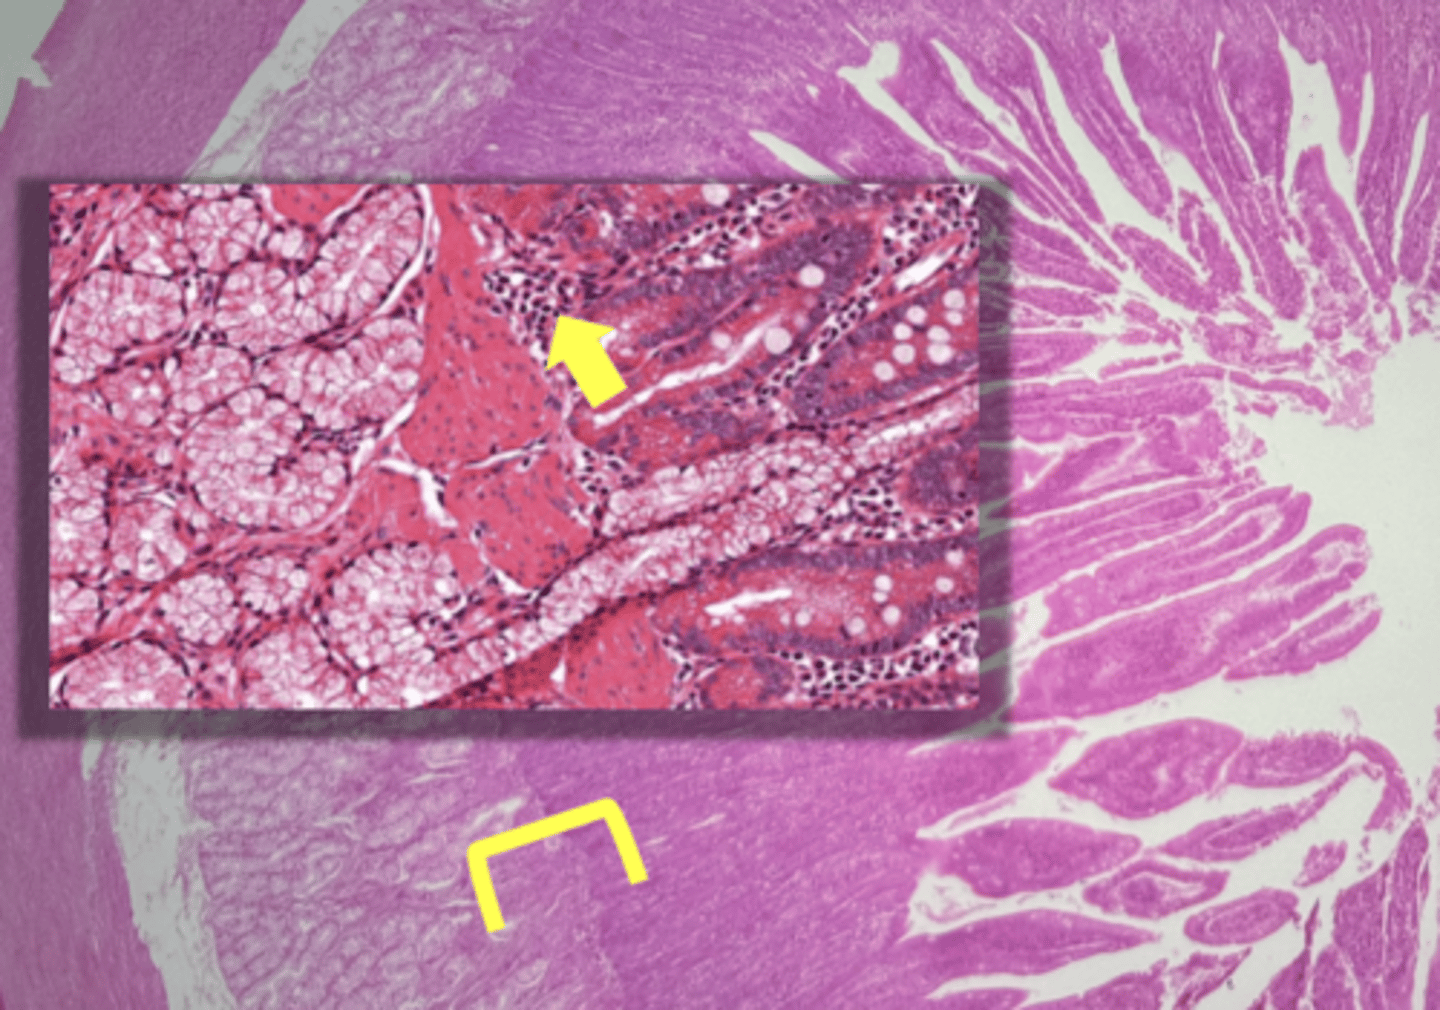

Pancreas

name the tissue

pancreatic islets

Acinar cells- digestive enzymes, amylase, lipase, & proteases

(pancreas)

type of cell & what it secretes?